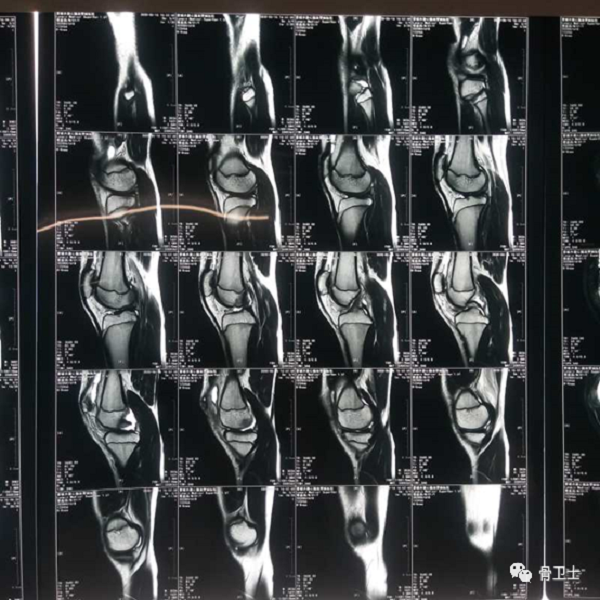

辅助检查:右膝关节核磁检查显示,右膝髌股关节不稳(高位髌骨、股骨滑车发育不良,髌骨向外侧稍移位),右膝髌上囊大量积液。

4.png

5.png

初步诊断:右膝关节髌骨半脱位